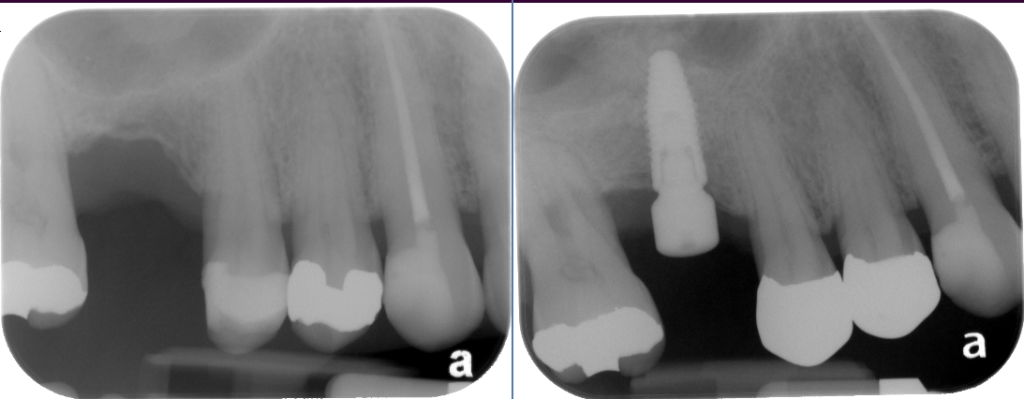

Sinus Lift Implant Vancouver Burnaby Periodontist Implant Dentist IMPreESS Perio

Dental Implant Centre in Vancouver Burnaby Sinus Lift Dental implant Surgery Dr. Noroozi Implant Specialist IMPrESS Perio Implant Center.001

Sinus Lift, Bone Graft, Implants Dr. Noroozi IMPrESS Perio Implant Center